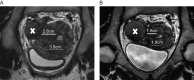

Uterine fibroids (also known as leiomyomas or myomas) are the most common form of benign uterine tumors. Clinical presentations include abnormal bleeding, pelvic masses, pelvic pain, infertility, bulk symptoms and obstetric complications.Almost a third of women with leiomyomas will request treatment due to symptoms. Current management strategies mainly involve surgical interventions, but the choice of treatment is guided by patient's age and desire to preserve fertility or avoid 'radical' surgery such as hysterectomy. The management of uterine fibroids also depends on the number, size and location of the fibroids. Other surgical and non-surgical approaches include myomectomy by hysteroscopy, myomectomy by laparotomy or laparoscopy, uterine artery embolization and interventions performed under radiologic or ultrasound guidance to induce thermal ablation of the uterine fibroids.There are only a few randomized trials comparing various therapies for fibroids. Further investigations are required as there is a lack of concrete evidence of effectiveness and areas of uncertainty surrounding correct management according to symptoms. The economic impact of uterine fibroid management is significant and it is imperative that new treatments be developed to provide alternatives to surgical intervention.There is growing evidence of the crucial role of progesterone pathways in the pathophysiology of uterine fibroids due to the use of selective progesterone receptor modulators (SPRMs) such as ulipristal acetate (UPA). The efficacy of long-term intermittent use of UPA was recently demonstrated by randomized controlled studies.The need for alternatives to surgical intervention is very real, especially for women seeking to preserve their fertility. These options now exist, with SPRMs which are proven to treat fibroid symptoms effectively. Gynecologists now have new tools in their armamentarium, opening up novel strategies for the management of uterine fibroids.